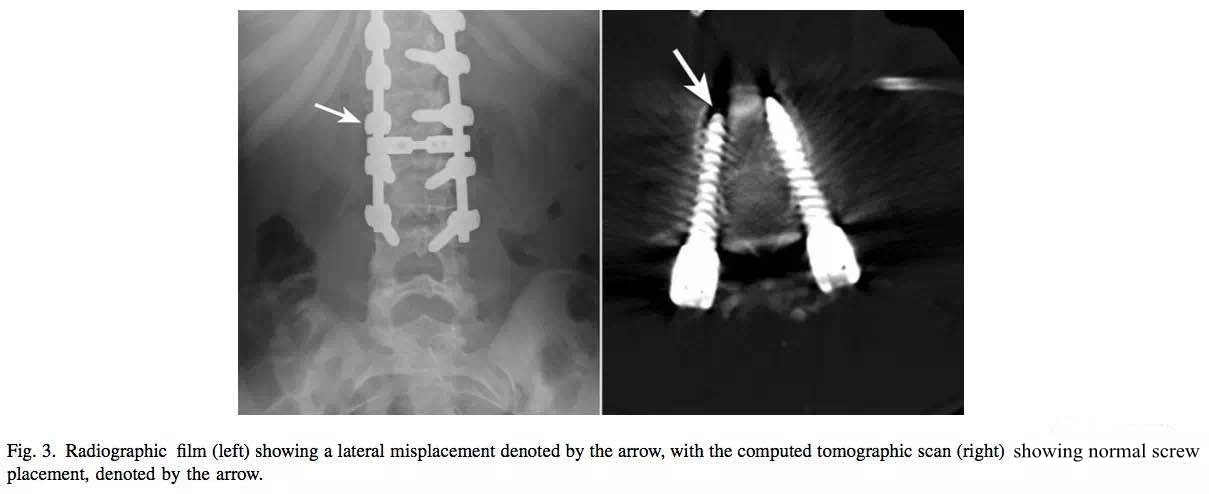

X线片显示钉子可能偏外出去了,但CT复查显示钉道良好。